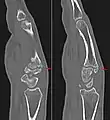

Additional images

Carpal boss in CT.